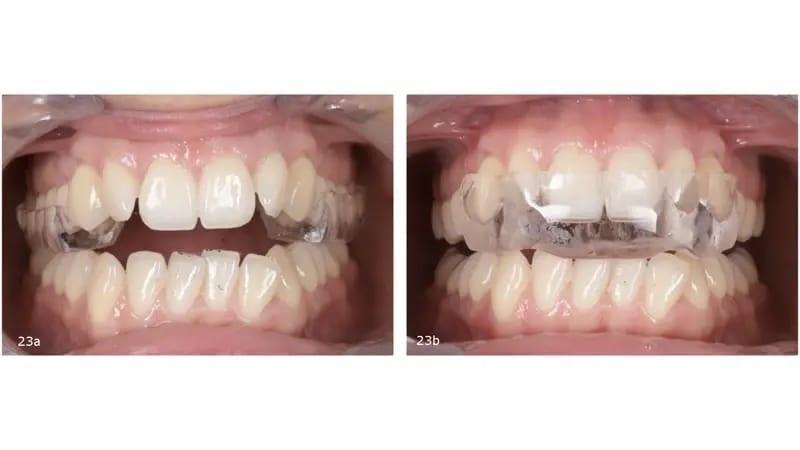

Была выбрана сплинт-шина, состоящая из двух частей, ее можно носить 24 часа в сутки в заднем сегменте днем и в переднем сегменте ночью (фото 23). Лечение шинами продолжалось в течение четырех месяцев, в течение которых было достигнуто стабильное положение мыщелков, пациентка добилась одномоментного закрывания рта и была достигнута полная ремиссия симптомов ВНЧС. В результате ротации нижней челюсти изменился прикус, что привело к увеличению переднего открытого прикуса (фото 24), увеличенное горизонтальное перекрытие верхних и нижних передних зубов (фото 25) и улучшение челюсти до классификации II класса (фото 26).

Фото 23a-b: Cплинт-шина, состоящая из двух частей. Задний сегмент (a). Передний сегмент (b).